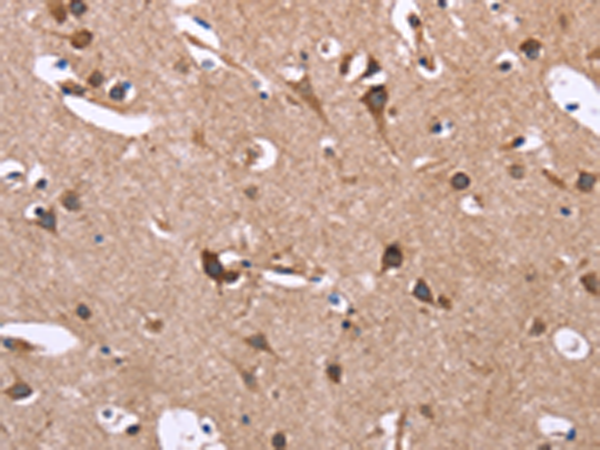

分类: 科研抗体货号: P10602别名: FAM115A应用: IHC反应种属: Human, Mouse